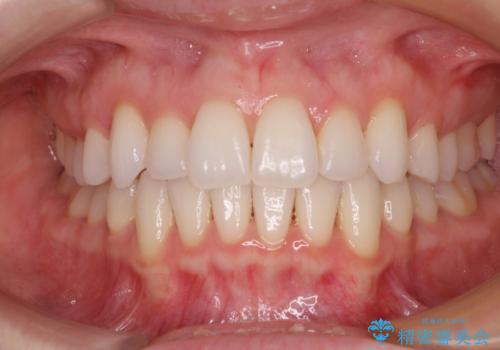

![[突き出た前歯を引っ込めたい] ワイヤー矯正とマウスピース矯正の併用治療の症例 治療後](https://seimitsushinbi.jp/wp/wp-content/uploads/2024/08/IMG_9725-500x350.jpg?v=1723179307)